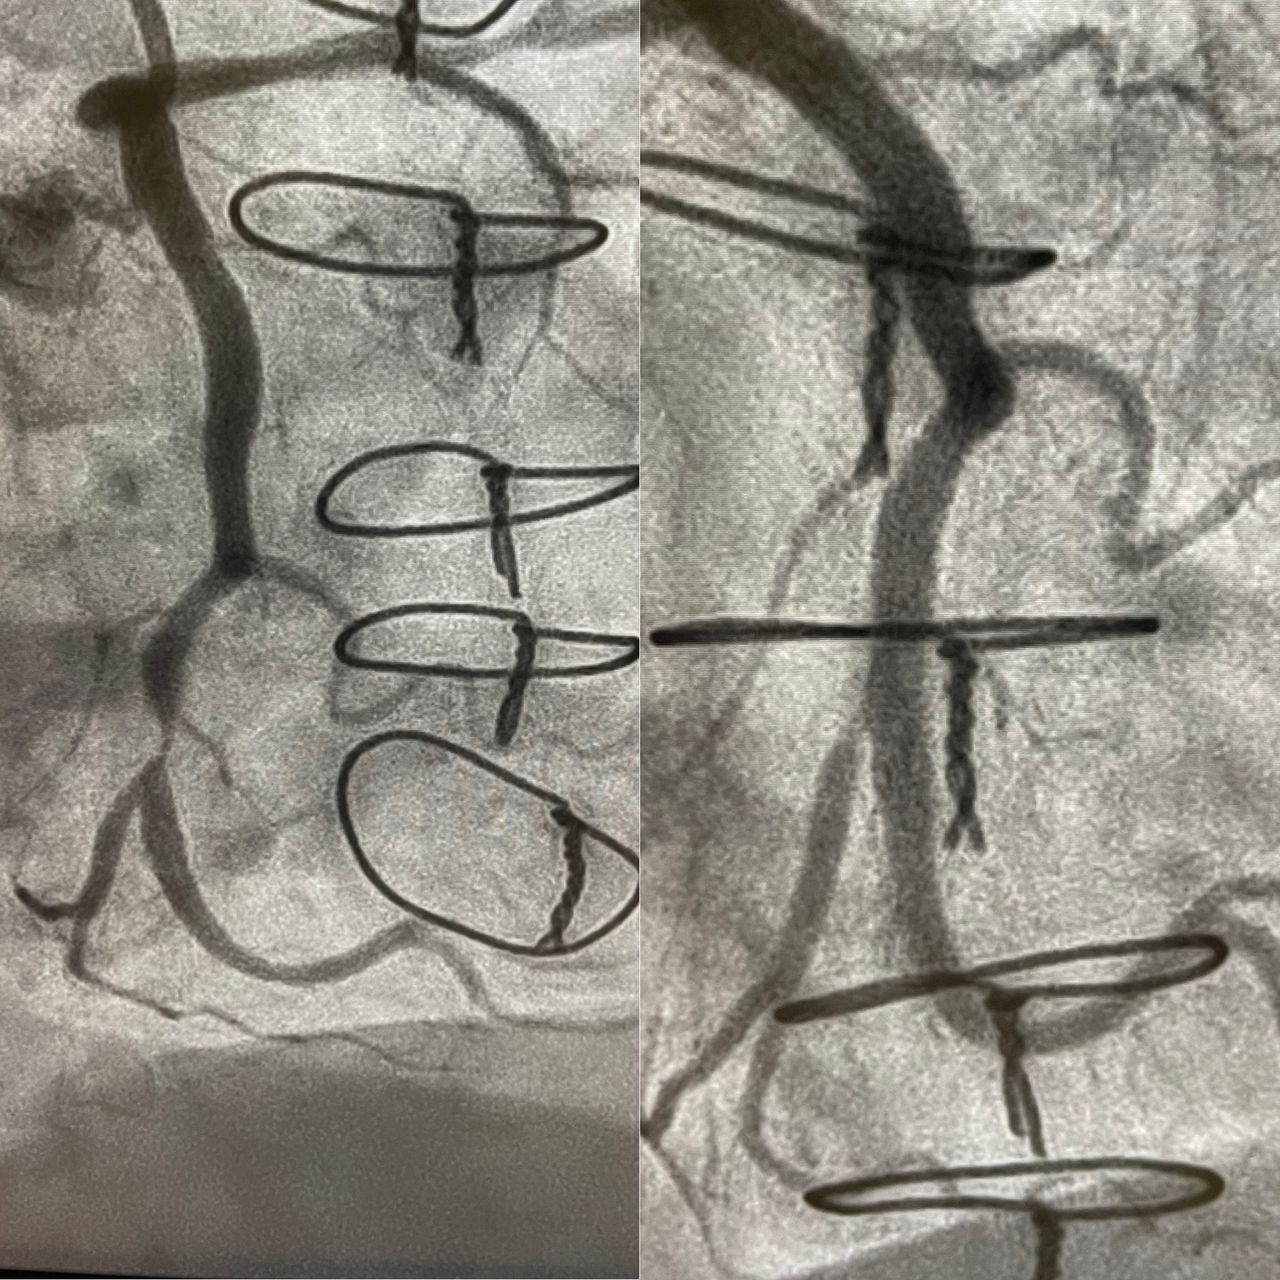

Realização de tratamentos minimamente invasivos no coração: cateterismo cardíaco (estudo das artérias do coração), angioplastia coronariana (implante de stent) e tratamentos das doenças que acometem as válvulas do coração.

Os procedimentos são realizados através da punção das artérias dos braços ou das pernas do paciente. É o tratamento mais seguro e eficaz para angina (dor no peito), infarto do miocárdio, obstruções (estenoses) nas artérias do coração e doenças das válvulas do coração ("sopros").

- Hemodinâmica e cardiologia intervencionista

- Doença arterial coronária

- Cardiologia intervencionista